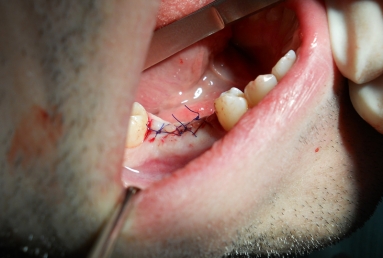

Initial situation: two missing teeth, second lower premolar and first lower molar. two dental implant are integrating in the mandibular bone for 4 months, then, gingival healing caps are applied for 3 weeks. an impression is taken for the dental lab in order to manufacture 2 porcelain fused to metal crowns. they will be screwed directly in the implant body.